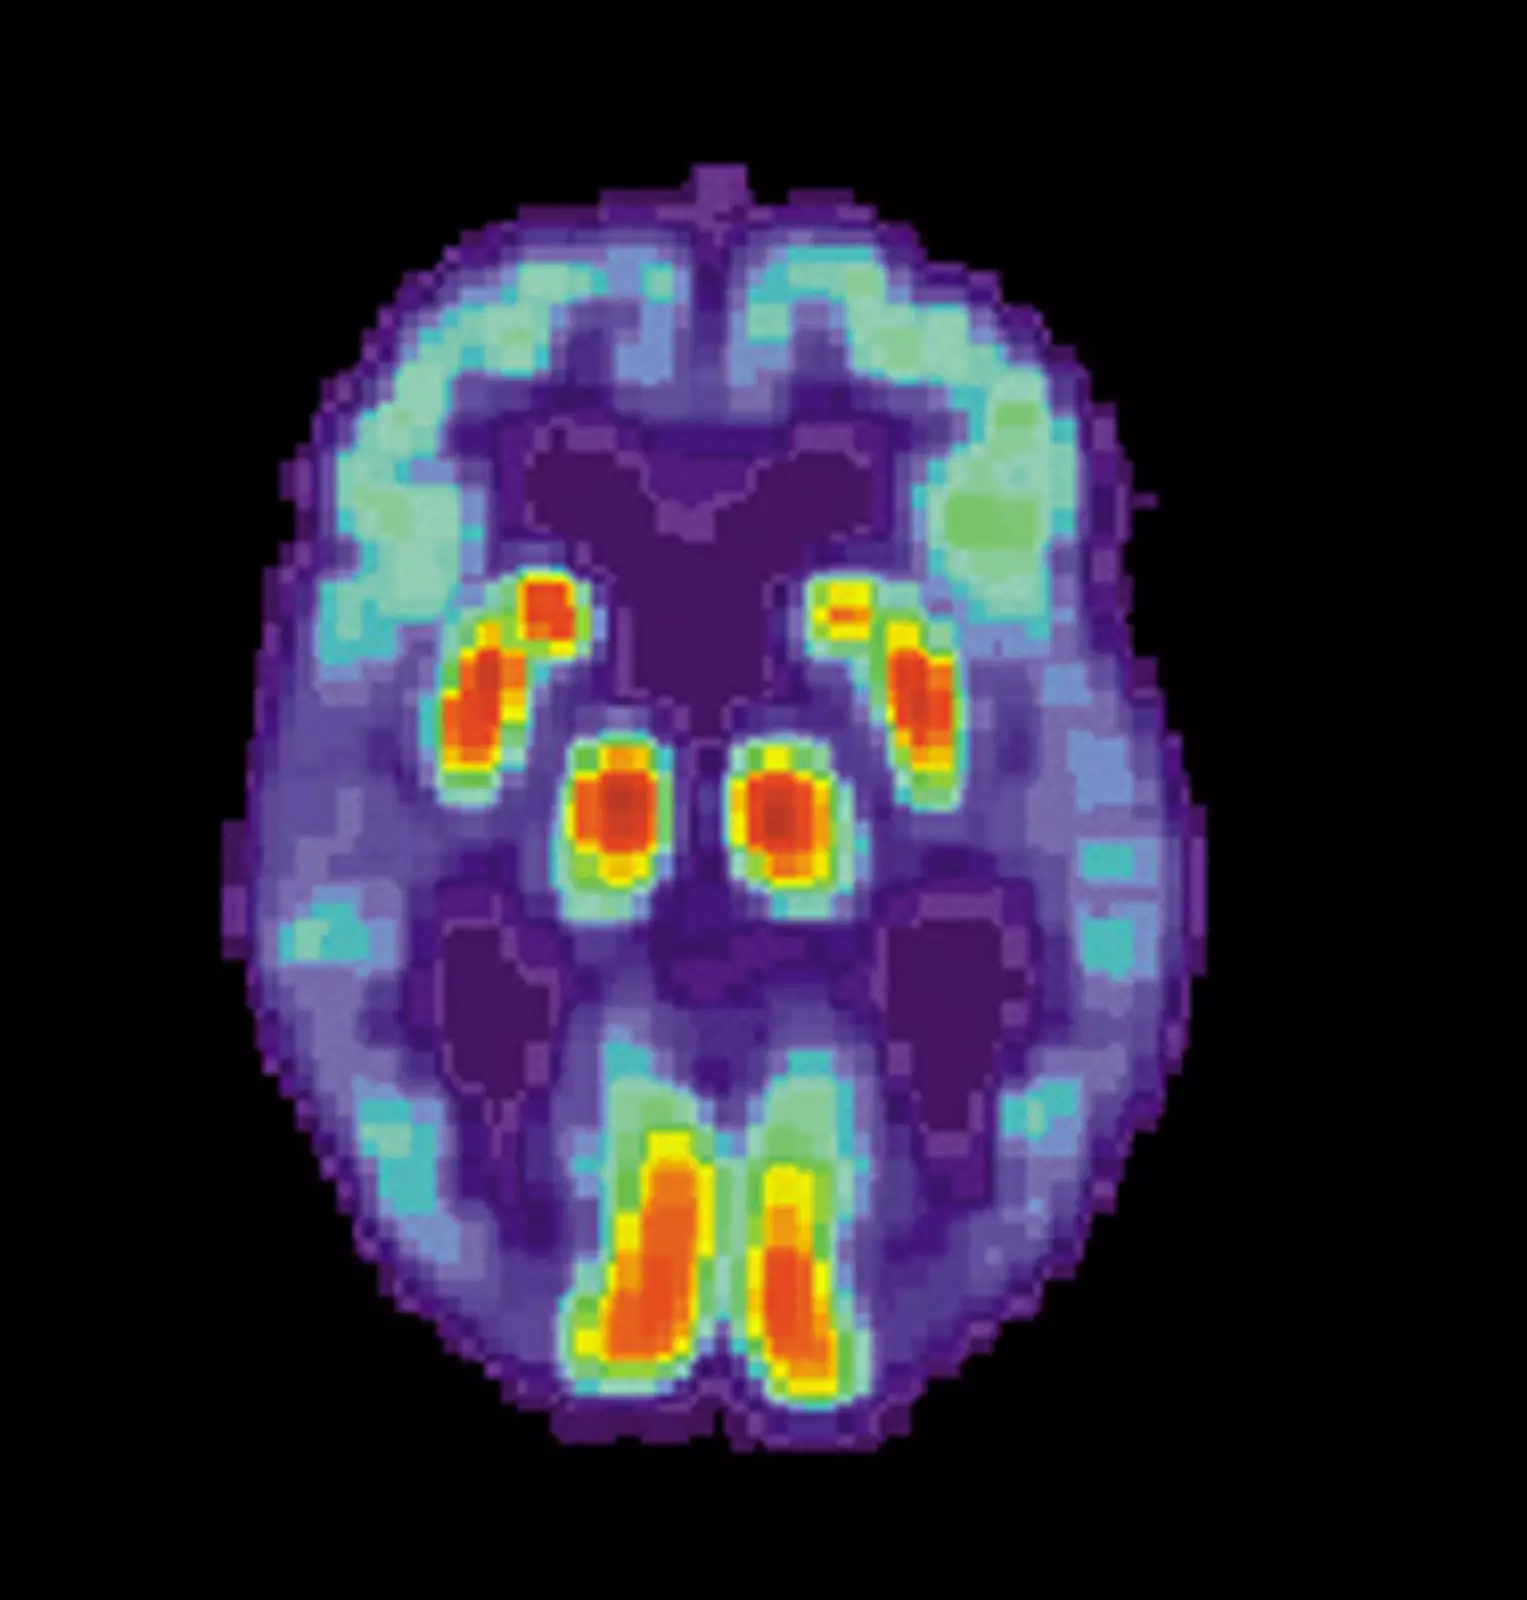

Появление позитронно-эмиссионной томографии (ПЭТ) позволило ученым воочию понаблюдать за потерей синапсов у живых пациентов даже с легкими симптомами болезни Альцгеймера.

Новый ПЭТ-визуализатор с использованием гликопротеина 2A (SV2A) помог измерить метаболическую активность в синапсах головного мозга у 45 человек с болезнью Альцгеймера легкой и средней степени тяжести.

Как обнаружила команда, потеря связей между клетками мозга, обнаруженная на томограммах, тесно связана с плохими результатами когнитивных тестов. ПЭТ-сканирование также показало себя более совершенным индикатором болезни Альцгеймера, чем все существующие тесты.